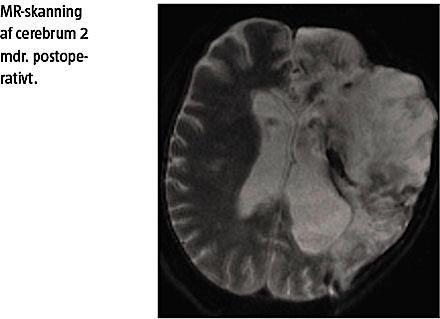

En akut MR-angiografi, som blev foretaget 14 timer postoperativt, viste et stort venstresidigt a. cerebri media-infarkt. Der blev verificeret total okklusion af a. carotis interna, a. cerebri media og prækommunikansdelen af a. cerebri anterior. Pga. infarktets volumen og høj risiko for inkarceration blev der foretaget profylaktisk hemikraniektomi og anlagt aflas-

tende dræn og intracerebral trykmåling. Patienten blev stabiliseret og overflyttet til et neurointensivt stepdown-afsnit, hvor tidlig højtspecialiseret neurorehabilitering blev påbegyndt. Fire måneder postoperativt var patienten fortsat i genoptræning og svært cerebralt skadet.